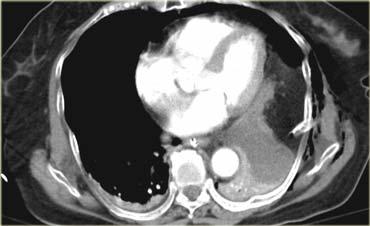

Bên trái là hình ảnh của nam bệnh nhân 22 tuổi không thắt dây an toàn, bị tai nạn giao thông tốc độ cao.

Bệnh nhân bị văng ra khỏi xe.

Lúc nhập viện, bệnh nhân trong tình trạng hôn mê, đã được đặt nội khí quản và mạch đùi hai bên giảm.

Hãy cuộn qua các hình ảnh bên trái và mô tả các dấu hiệu.

Các dấu hiệu bao gồm:

- Dịch màng phổi với tỷ trọng cao ở vùng thấp, gợi ý tràn máu màng phổi.

- Vùng ngấm thuốc cản quang gần lách, gợi ý chảy máu đang hoạt động.

- Nhồi máu thận hai bên (các hình ảnh bổ sung cho thấy thêm các ổ nhồi máu ở thận phải).

- Tổn thương mô mềm bao quanh động mạch chủ.

Các câu hỏi đặt ra là:

- Cần chẩn đoán phân biệt những bệnh lý nào?

- Tính chất hai bên của nhồi máu thận có ý nghĩa gì?

Nhồi máu thận một bên có thể là hậu quả của một tổn thương khu trú.

Tuy nhiên, khi có nhiều ổ nhồi máu hai bên, cần nghĩ đến nguồn gốc thuyên tắc từ xa.

Vị trí thường gặp nhất sau chấn thương của các cục thuyên tắc này là động mạch chủ ngực tại eo động mạch chủ, do đây là vị trí cố định của động mạch chủ.

Tuy nhiên, ở bệnh nhân này, nguyên nhân là do bóc tách động mạch chủ do chấn thương tại mức cơ hoành.

Đây là vị trí thường gặp thứ hai của tổn thương động mạch chủ do tính chất tương đối cố định tại vị trí này.